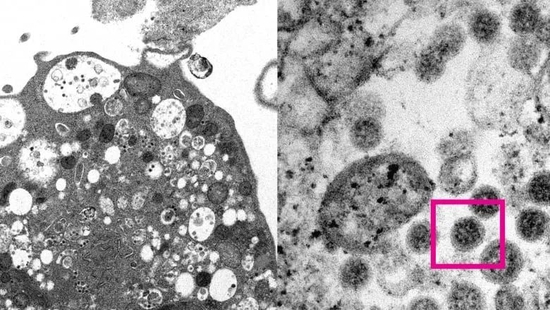

显微镜下的Omicron变种新冠病毒。